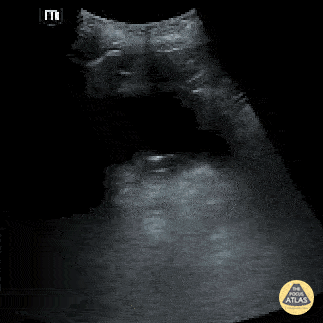

A bladder diverticulum is demonstrated deep to the bladder as the ultrasound probe is fanned. Contributed by: Brittany Garza, DO; Saleem Nasseh, MD; Sadie Ellerson, MS4